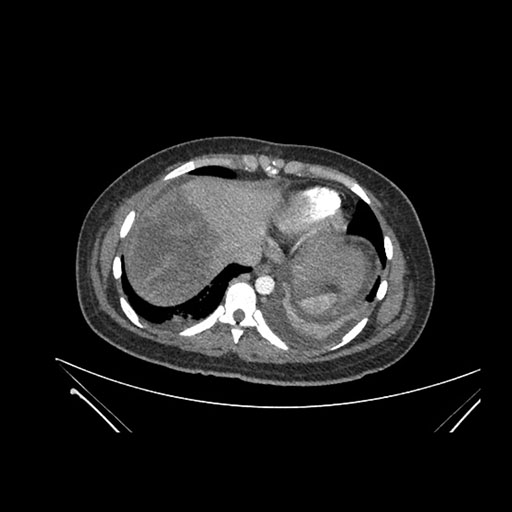

Imaging Analysis

Look through the patient's CT scan to identify any areas of concern for the necessary procedure.

Axial Venous

Based on initial findings, which issue(s) would you be most concerned about?